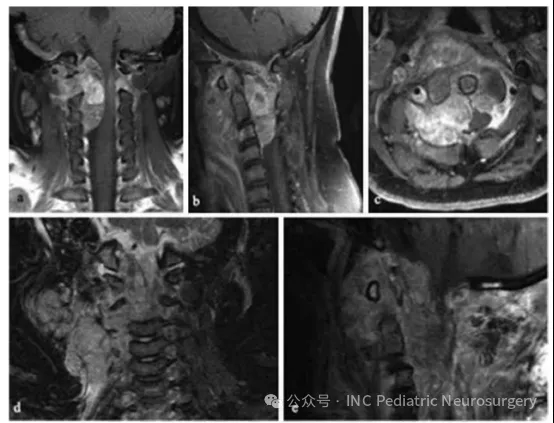

患者10

患者于2015年就诊,14个月大,主诉巨头畸形(macrocephaly)2个月、中央性肌张力低下、声音虚弱、吞咽困难,以及发育倒退。检查发现显著交通性脑积水与巨脑症,并伴有左侧小脑桥脑角(CPA)巨大异质性强化病灶,影像上可见出血伪影(blooming artifact)、液-液平面(fluid-fluid levels),并压迫脑干(图6)。

患者接受左侧后乙状窦开颅术(retrosigmoid craniectomy)。术中病理提示淋巴样细胞,术中仅能行次全切除(subtotal resection),脑干部仍有残留肿瘤。术后,患者持续存在颅神经功能缺损、吞咽困难(需行胃造口术),以及原因不明的交通性脑积水(需行脑室-腹腔分流术)。

最终固定病理结果显示非典型脊索瘤(atypical chordoma),免疫组化Brachyury、pan-CK、EMA、INl1基因产物(BAF47/INl1)均为阳性。在已报道的儿童脊索瘤病例中,她是年龄最小的患者之一,也是唯一发生在CPA的病例。

由于患儿年龄极小、肿瘤位置特殊且病理为非典型,治疗决策由多学科团队(MDT)制定。她接受了3个周期ICE化疗。虽然术后临床情况相对稳定,但随访影像显示手术部位病灶影像学进展,同时在左侧颞叶凸面出现新的硬膜基底结节性强化灶,考虑可能为脑膜播散。

此时,她接受3个月常规放疗,并对左侧CPA区域实施伽马刀强化照射。遗憾的是,肿瘤在放疗期间继续进展,MRI显示肿瘤向侧方侵入Meckel腔,并向左小脑幕后方延伸。

全外显子测序显示SMARCA4突变,随后开始Vorinostat+顺-维甲酸(cis-retinoic acid)化疗。尽管采取了积极治疗,肿瘤仍快速进展,累及左侧海绵窦、眶区及颅中窝。患者在短期姑息治疗后去世,距首次诊断约1年。

图6.患者10的左桥小脑角区脊索瘤影像学随访资料。(a)术前轴位T1加权钆增强MRI;(b)术前矢状位T1加权钆增强MRI;(c)术前轴位T2加权MRI;(d)术前轴位CT扫描;(e)术后5个月轴位T1加权钆增强MRI,显示左颞部新发硬膜病变(箭头);(f)术后9个月轴位T1加权钆增强MRI;(g)术后9个月矢状位T1加权钆增强MRI;(h)术后12个月轴位CT扫描。